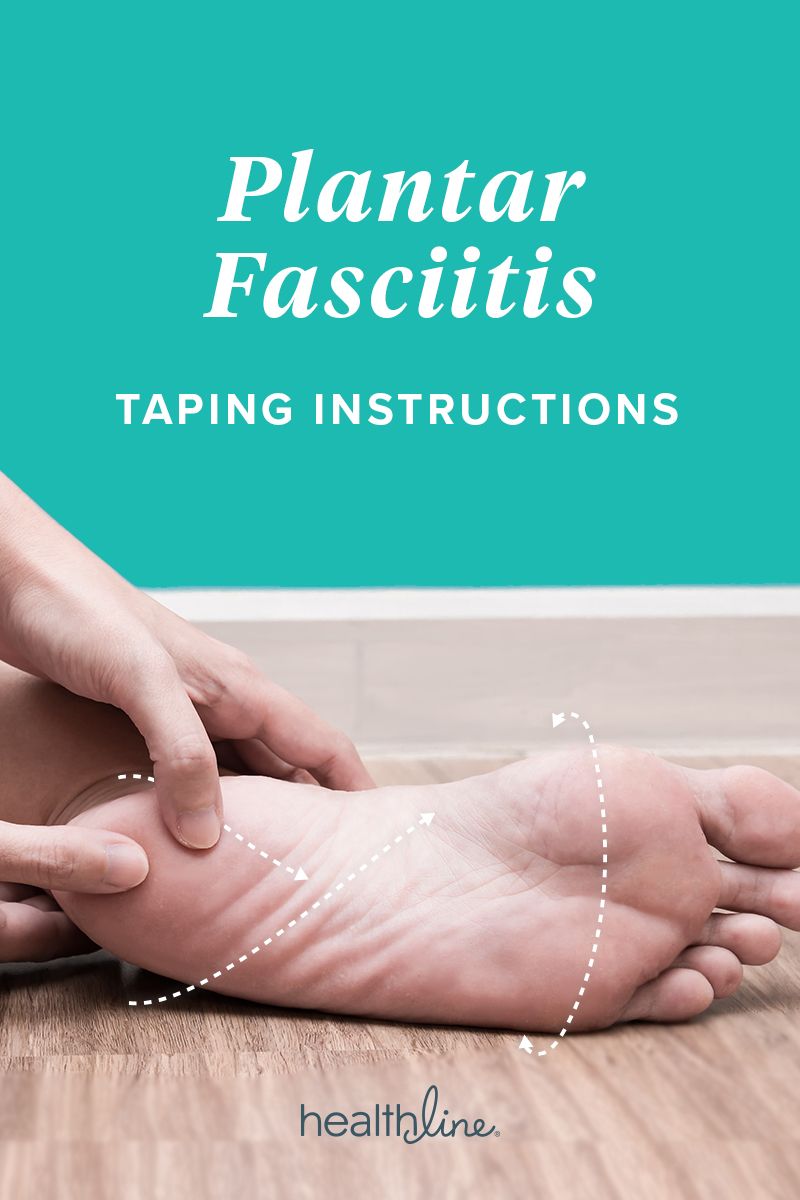

Product Name: Taping foot arch best sale

4 Ways of taping your foot plantar fasciitis or foot arch support best sale, 4 Ways of taping your foot plantar fasciitis or foot arch support best sale, The Best Foot Arch Support Taping How to low dye tape for plantar fascia or arch support easy best sale, Foot Arch Supportive Taping YouTube best sale, Plantar Fasciitis Taping Benefits Materials How To and Diagram best sale, Arch Support Taping Physical Sports First Aid Blog best sale, How to Tape Your Arches for Flat Feet Easy Guide Video Bilt Labs best sale, Taping foot for arch deals support best sale, Arch Taping Technique with RockTape K Tape Kinesiology Tape YouTube best sale, Tab Arch Taping Technique Maximum Training Solutions best sale, 4 Ways of taping your foot plantar fasciitis or foot arch support best sale, Arch Support Taping Physical Sports First Aid Blog best sale, Foot Arch Supportive Taping best sale, Tape for shop arch support best sale, Flat Feet Need Orthotics 4 Easy Steps Burnaby Physio best sale, Taping for deals arch pain best sale, Plantar Fasciitis KT Taping Guide Heel That Pain best sale, 4 Ways of taping your foot plantar fasciitis or foot arch support best sale, Treating Plantar Fasciitis With Kinesiology Tape best sale, Athletic taping for arch support to help flat arch or pes planus. This tape job can be quite effective in helping relieve pain in the arches due to flat feet or Overpronation syndrome. It is also best sale, Effects of Kinesiotape versus Low Dye Tape on Pain and Comfort Measures in Patients with Plantar Fasciitis A Randomized Clinical Trial best sale, All taping techniques were applied with the foot in some supination and. Download Scientific Diagram best sale, How to tape the foot medial arch pain dropped arch foot pronation sports taping series best sale, Pin page best sale, How taping can assist Plantar Fasciitis and foot pain TPM best sale, Fan arch support medial longitudinal arch taping technique used in the. Download Scientific Diagram best sale, Plantar Fasciitis Taping For Superior Arch Support best sale, Kinesio tape deals foot arch best sale, How to Tape Your Arches for Flat Feet Easy Guide Video Bilt Labs best sale, QuickTape LP best sale, Plantar Fasciitis Taping Benefits Materials How To and Diagram best sale, Arch Support Taping best sale, How Taping Your Foot for Plantar Fasciitis Really Works Vive Health best sale, About QUICK TAPE Support Straps Support the Foot best sale, Taping techniques. Low dye technique A an anchor strip around the. Download Scientific Diagram best sale.

Taping foot arch best sale